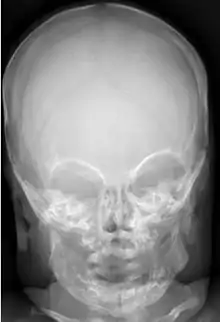

Macrocephaly

Macrocephaly is a condition in which circumference of the human head is abnormally large.[1] It may be pathological or harmless, and can be a familial genetic characteristic. People diagnosed with macrocephaly will receive further medical tests to determine whether the syndrome is accompanied by particular disorders. Those with benign or familial macrocephaly are considered to have megalencephaly.

| An MRI of a patient with benign familial macrocephaly (male with head circumference > 60 cm) | |

Diagnosis

Macrocephaly is customarily diagnosed if head circumference is greater than two standard deviations (SDs) above the mean.[9] Relative macrocephaly occurs if the measure is less than two SDs above the mean, but is disproportionately above that when ethnicity and stature are considered. Diagnosis can be determined in utero or can be determined within 18–24 months after birth in some cases where head circumference tends to stabilize in infants.[10] Diagnosis in infants includes measuring the circumference of the child's head and comparing how significant it falls above the 97.5 percentile of children similar to their demographic. If falling above the 97.5th percentile then the patient will be checked to determine whether there is any intracranial pressure present and whether or not immediate surgery is needed.[11] If immediate surgery is not needed then further testing will be done to determine whether the patient has either macrocephaly or benign macrocephaly.